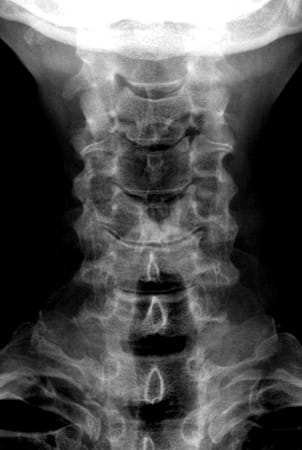

Auf diese Weise wird die Belastung der Wirbelsäule wie bei einer natürlichen Bandscheibe aufgenommen. Bei chronischen Bandscheibenerkrankungen sollte zuvor eine mindestens 3-monatige konservative Therapie versucht werden. Ist diese erfolglos oder treten nicht beherrschbare Schmerzen oder Nervenstörungen auf, so übernehmen die Krankenkassen in der Schweiz die Operation, sofern nicht mehr als zwei Bandscheiben betroffen sind und keine primäre Arthrose der Facettengelenke vorliegen. Bei akuten Bandscheibenvorfällen mit schweren Nervenstörungen oder Lähmungen besteht ebenfalls die Indikation zur Operation. Diese wird von vorne durch einen kleinen, etwa 2-3 cm langen, queren Hautschnitt in einer Hautfalte am Hals vorgenommen. Rechts oder links seitlich der Luft- und Speiseröhre gelangt man sehr schonend auf die Halswirbelsäule. Auf diese Weise kann die betroffene Bandscheibe vollständig entfernt werden und der Rückenmarkskanal sowie die entsprechenden Nervenwurzeln entlastet werden. Anschließend wird der Bandscheibenraum mit speziellen Instrumenten auf seine normale Höhe aufgedehnt, um die Nervenwurzeln zu dekomprimieren und Platz für die Prothese zu schaffen. Nach Ausmessen der passenden Größe und präziser Vorbereitung des Implantatbettes wird das Implantat unter Röntgenkontrolle eingesetzt. Beispiel einer degenerativen Bandscheibenerkrankung an der HWS und Versorgung mit drei visko-elastischen Bandscheibenprothesen

vor OP vorn